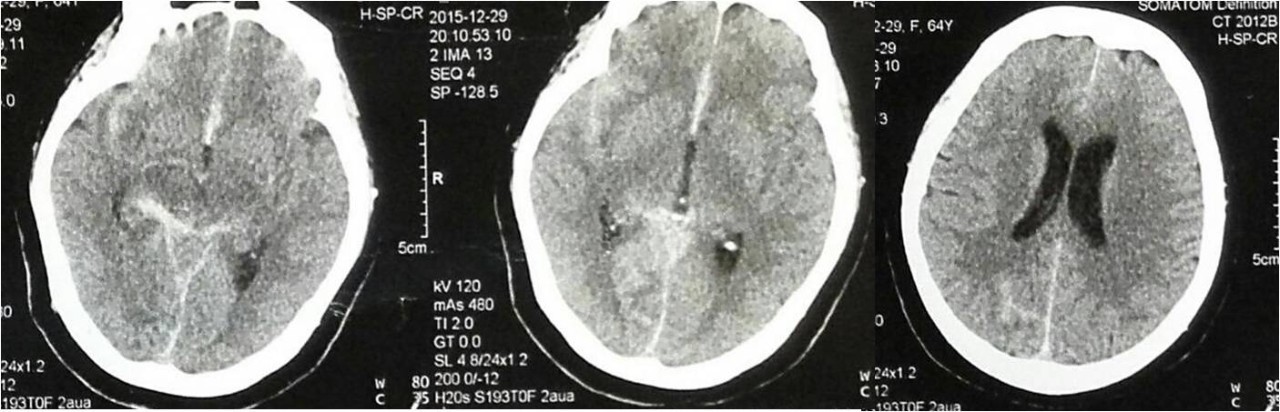

(一)超急性期脑梗死支架取栓

病例1:超急性期脑梗死支架取栓术

》男性,64岁,因突然不能言语伴左侧肢体活动不灵2小时入院。既往有高血压病病史20年,糖尿病病史30年。

》入院时查体:血压176/105mmHg,嗜睡,双眼向右侧视,左侧肢体肌力0级,左侧病理征阳性。

》入院后行一站式头颅CT(头颅CT、CTA、CTP)。

》经家属签署支架取栓知情同意书后,推入导管室,行血管内检查及取栓治疗。

术前侧支循环评估

全麻下行Solitaire支架取栓术

》取栓后患者右侧大脑中动脉再通,血流恢复,但术后患者症状无改善。

病例2:超急性期脑梗死取栓后放颅内支架

》男性,72岁,因突然不能言语伴左侧肢体活动不灵1.5小时入院。既往糖尿病病史40年。

》入院时查体:血压165/100mmHg,嗜睡,双眼向右侧视,左侧肢体肌力0级,左侧病理征阳性。

》取栓后发现大脑中动脉M1段重度狭窄,放置颅内阿波罗支架后狭窄消失。